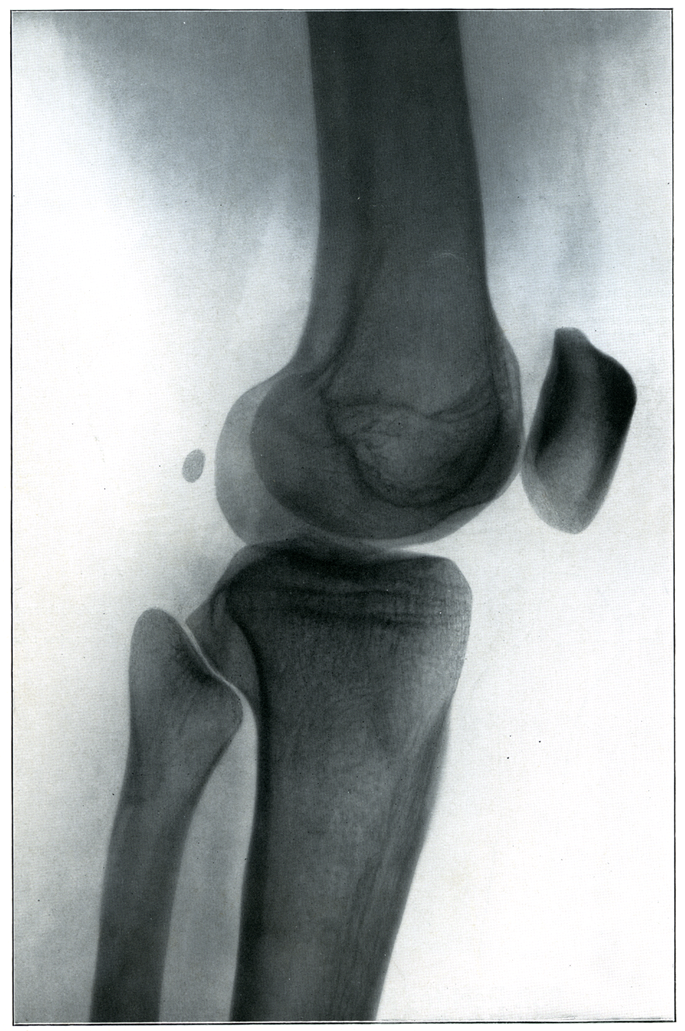

【Knee

膝;ヒザ

Genu】

→(大腿と下腿の間の関節部。)